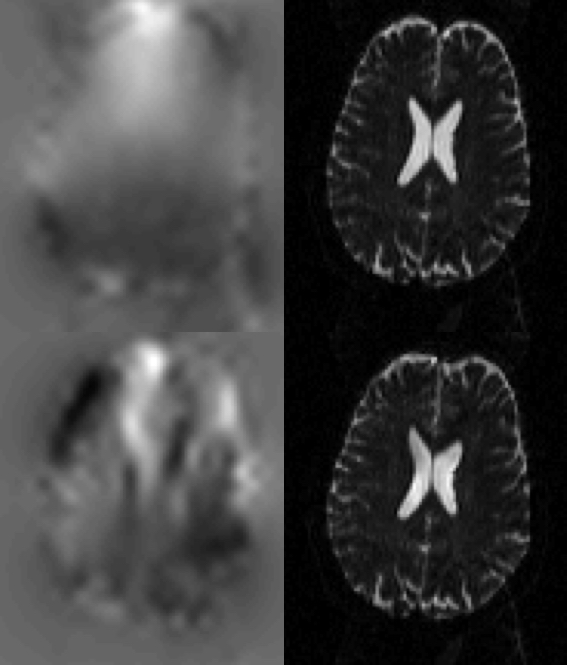

If instead using the true field for the GE-EPI images one can see below that the corrected images also look good. But looking closely one can see that in the areas of severe signal modulation it doesn't do quite as good a job (of matching the intensities) as the "faulty" field. Hence it is easy to see why topup would find the "faulty" field.

![]() |

| The top row shows the true field and the resulting corrected GE-EPI images. Note how the outlines of the brains look similar, indicating that the distortion correction has been successful. Note also that the intensities inside the brain are quite different, with the A->P image having more signal dropout posterior of the peak in the off-resonance field while in the P->A image it is mostly anterior of the peak. This indicates that the signal modulation is dominated by the gradient (in the off-resonance field) along the PE-direction, which leads to a shift in echo time. The bottom row shows the "faulty" field, that which was estimated from the GE-EPI image pair, along with the resulting corrected images. Note how topup has "successfully" managed to reduce the difference in signal modulation, leading to an estimated field that is vastly different to the truth. |